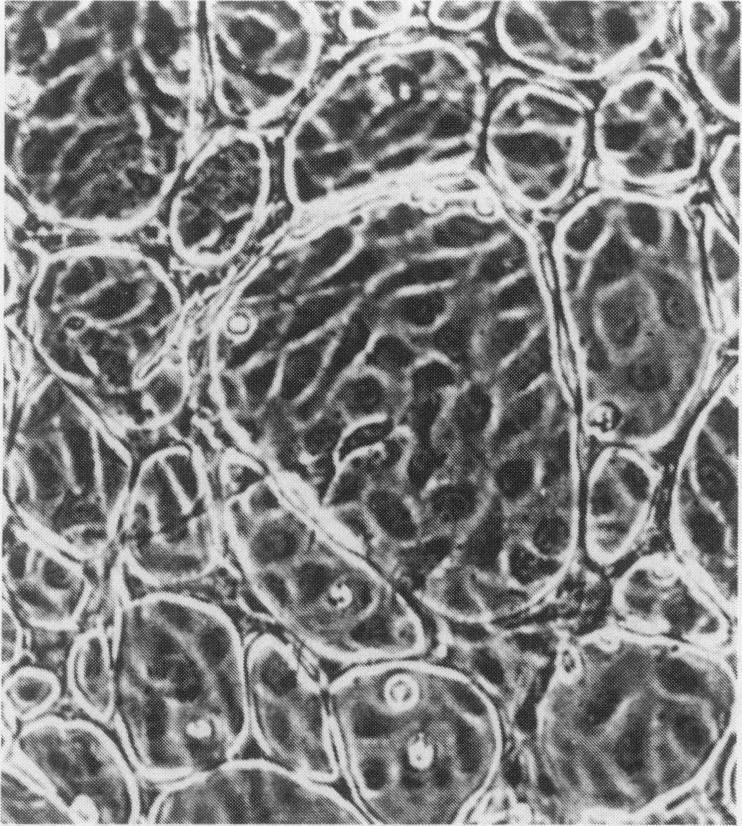

Immunocytochemistry has been used to identify endothelial cells in sections of human umbilical cord and in cultures of the venous and arterial endothelium, using Factor VIII and Ulex europaeus as endothelial markers. The connective tissue components, including various collagen types, fibronectin and laminin, were identified and localized in the cord and in both venous and arterial cultured endothelium. Interstitial collagens synthesized by the cultured cells were isolated and quantified. Angiogenic ability was examined. The effect of a noxious stimulus, 24 h hypoxia, was quantified in cultured venous endothelium. The results showed that cultured arterial endothelium possesses a vacuolated cytoplasm which is absent in venous endothelium. The major collagens observed in venous culture were types III and V; the latter was found mainly in the cell layer. Venous endothelium was angiogenic. It responded to hypoxia by producing fewer cells, more protein/10(6) cells but less collagen, both in absolute terms and as a percentage of protein/10(6) cells, thus behaving like cultured porcine and bovine aortic endothelium. Fibronectin was the major 'glue' associated with endothelium. We conclude that culture can reveal the synthetic potential of endothelium which the cord itself does not often show; moreover culture appears essential to demonstrate that arterial and venous endothelium behave differently from each other.